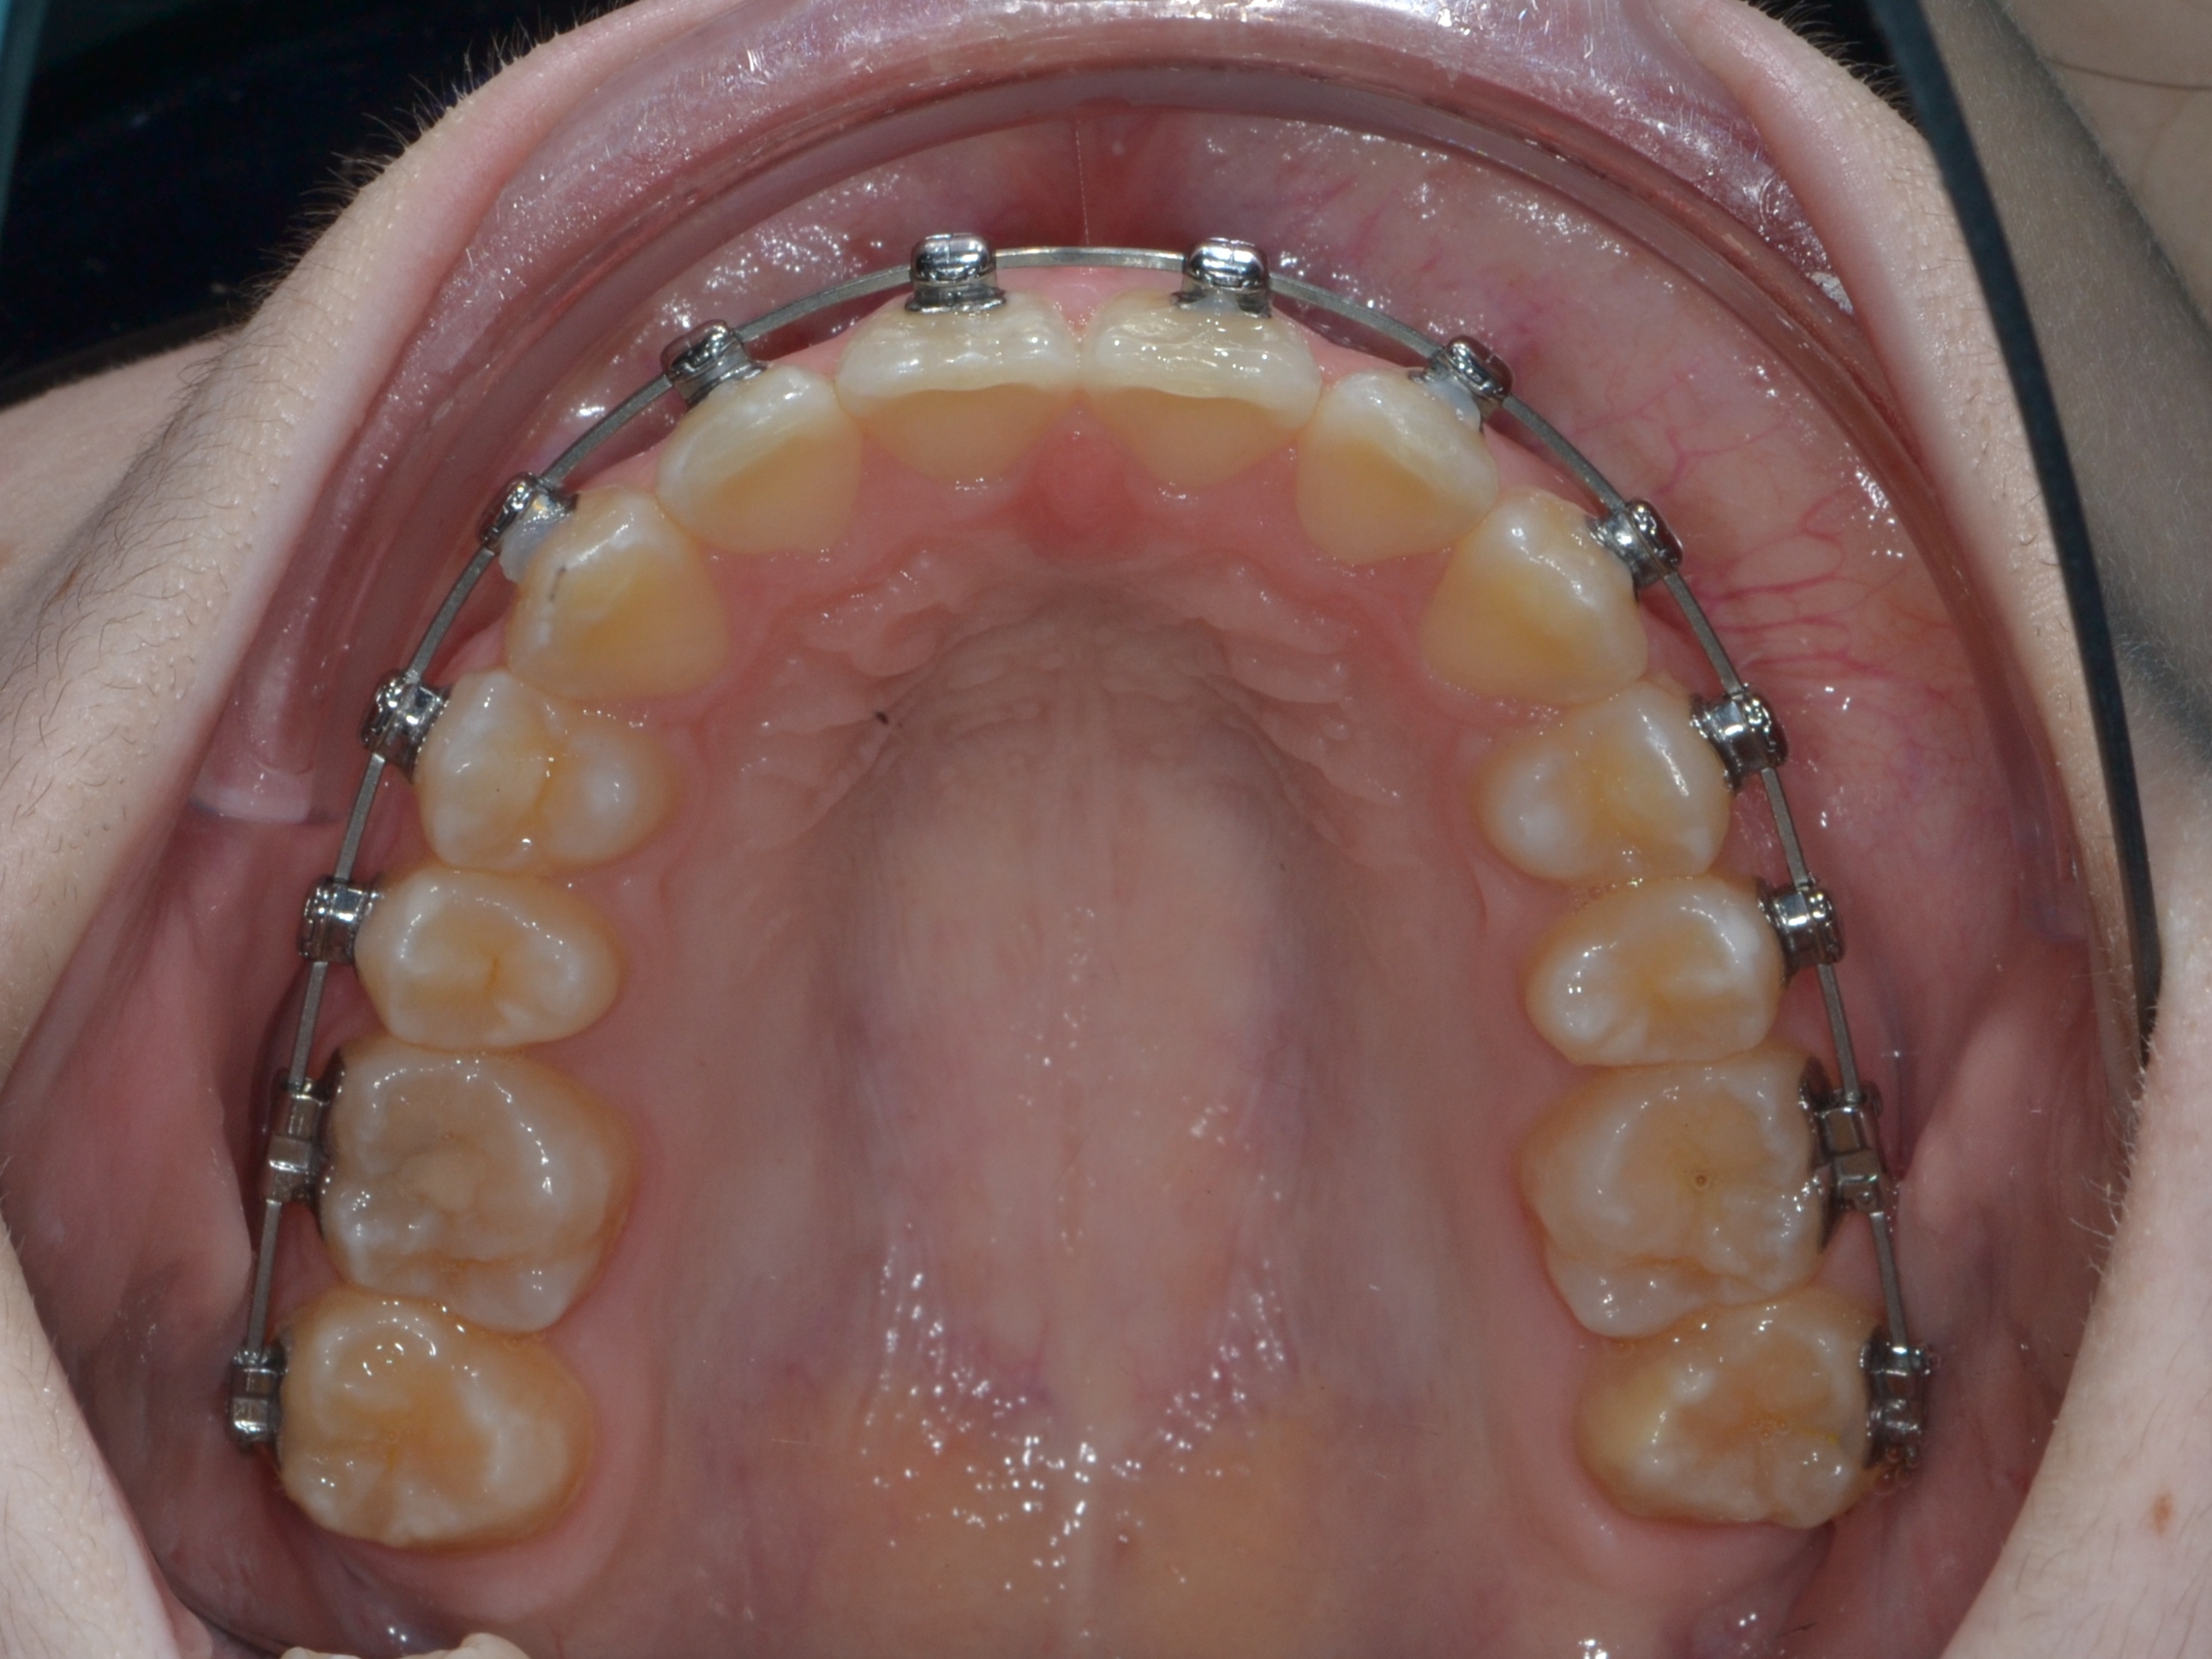

Брекет-система Ultra

До фиксации

Июль 2024 г.

2

6 месяцев

Декабрь 2024 г.